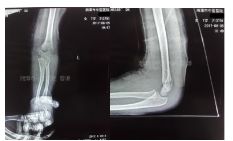

入院拍片如下:

采用四步复位法整复后拍片复查

治疗一月拍片复查

治疗三个月后拍片复查